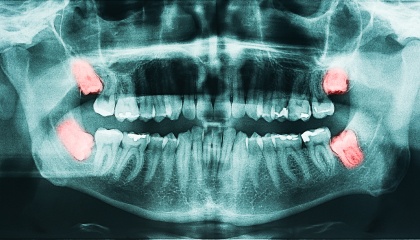

The decision to remove wisdom teeth is influenced by several factors and is usually made after a comprehensive examination by your dentist at Today Dental of Haslet. Wisdom teeth, also known as third molars, may need removal if they cause issues like:

• Impaction: Stuck in the jawbone and unable to erupt properly.

• Crowding: Cause other teeth to shift or become misaligned.

• Pain: Cause discomfort or pressure.

• Infection: Become infected due to difficulty cleaning them properly.

• Damage to nearby teeth: Damage or harm surrounding teeth.

Even if your wisdom teeth aren't causing immediate problems, we may recommend removal to prevent potential future complications, a frequent occurrence.